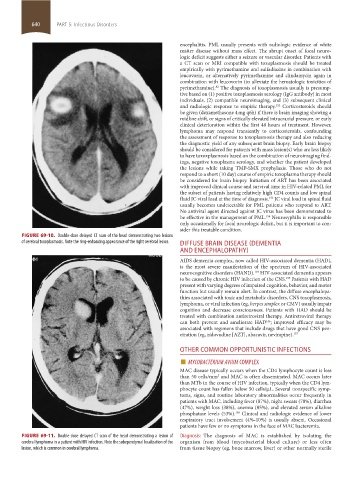

FIGURE 69-10. Double-dose delayed CT scan of the head demonstrating two lesions

of cerebral toxoplasmosis. Note the ring-enhancing appearance of the right cerebral lesion. DIFFUSE BRAIN DISEASE (DEMENTIA